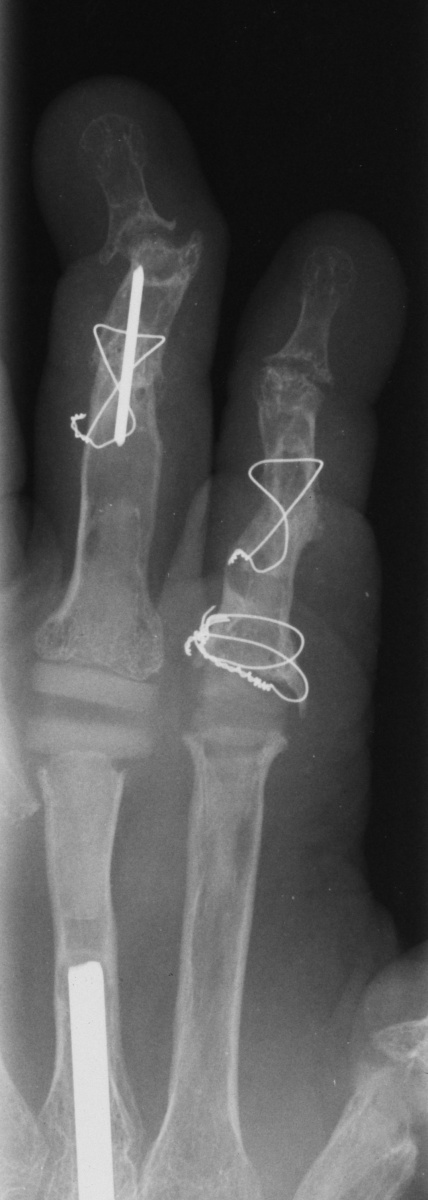

Xrays show radiocarpal collapse, proximal migration of the proximal phalanges, flail PIP joints and loss of the proximal half of the dorsal cortex of the proximal phalanges.

For the second stage of her reconstruction, the index proximal phalanx did not have adequate dorsal cortex to support an implant arthroplasty, and bone graft from the metacarpal head was used to reconstruct this.

Final radiographs, three months postoperative.